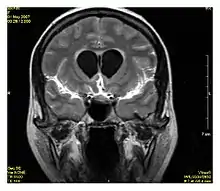

| Diffusion weighted (DWI) | Conventional | DWI | Measure of Brownian motion of water molecules.[17] | High signal within minutes of cerebral infarction (pictured).[18] | ![]() |

Diffusion weighted

Diffusion MRI measures the diffusion of water molecules in biological tissues.[41] Clinically, diffusion MRI is useful for the diagnoses of conditions (e.g., stroke) or neurological disorders (e.g., multiple sclerosis), and helps better understand the connectivity of white matter axons in the central nervous system.[42] In an isotropic medium (inside a glass of water for example), water molecules naturally move randomly according to turbulence and Brownian motion. In biological tissues however, where the Reynolds number is low enough for laminar flow, the diffusion may be anisotropic. For example, a molecule inside the axon of a neuron has a low probability of crossing the myelin membrane. Therefore, the molecule moves principally along the axis of the neural fiber. If it is known that molecules in a particular voxel diffuse principally in one direction, the assumption can be made that the majority of the fibers in this area are parallel to that direction.

The recent development of diffusion tensor imaging (DTI)[43] enables diffusion to be measured in multiple directions, and the fractional anisotropy in each direction to be calculated for each voxel. This enables researchers to make brain maps of fiber directions to examine the connectivity of different regions in the brain (using tractography) or to examine areas of neural degeneration and demyelination in diseases like multiple sclerosis.

Another application of diffusion MRI is diffusion-weighted imaging (DWI). Following an ischemic stroke, DWI is highly sensitive to the changes occurring in the lesion.[44] It is speculated that increases in restriction (barriers) to water diffusion, as a result of cytotoxic edema (cellular swelling), is responsible for the increase in signal on a DWI scan. The DWI enhancement appears within 5–10 minutes of the onset of stroke symptoms (as compared to computed tomography, which often does not detect changes of acute infarct for up to 4–6 hours) and remains for up to two weeks. Coupled with imaging of cerebral perfusion, researchers can highlight regions of "perfusion/diffusion mismatch" that may indicate regions capable of salvage by reperfusion therapy.